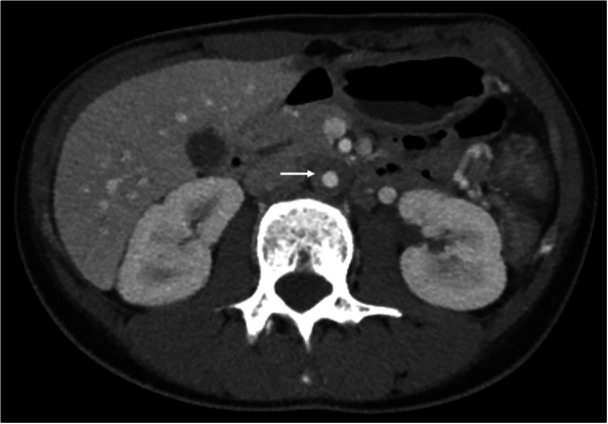

Extraintestinal manifestations in inflammatory bowel disease (IBD) most frequently involve the joints, skin, and organs such as the liver and pancreas. Inflammation of the aorta is less commonly described in pediatrics, although it has been described in adults. We report a case of an adolescent female with Crohn's disease who presented with worsening diarrhea, vomiting, and weight loss, found to have aortitis on imaging. We review the pathogenesis and clinical features of Takayasu arteritis, as well as some of its similarities to IBD to raise awareness, as early detection of this less-known extraintestinal manifestation has been associated with better outcomes.

炎症性肠病(IBD)的肠外表现最常涉及关节、皮肤和器官,如肝脏和胰腺。主动脉炎症在儿科中不太常见,尽管在成人中有过描述。我们报告一个患有克罗恩病的青春期女性的病例,她表现为腹泻、呕吐和体重减轻,影像学检查发现她患有大动脉炎。我们回顾了Takayasu动脉炎的发病机制和临床特征,以及它与IBD的一些相似之处,以提高人们的认识,因为早期发现这种鲜为人知的肠外表现与更好的结果相关。